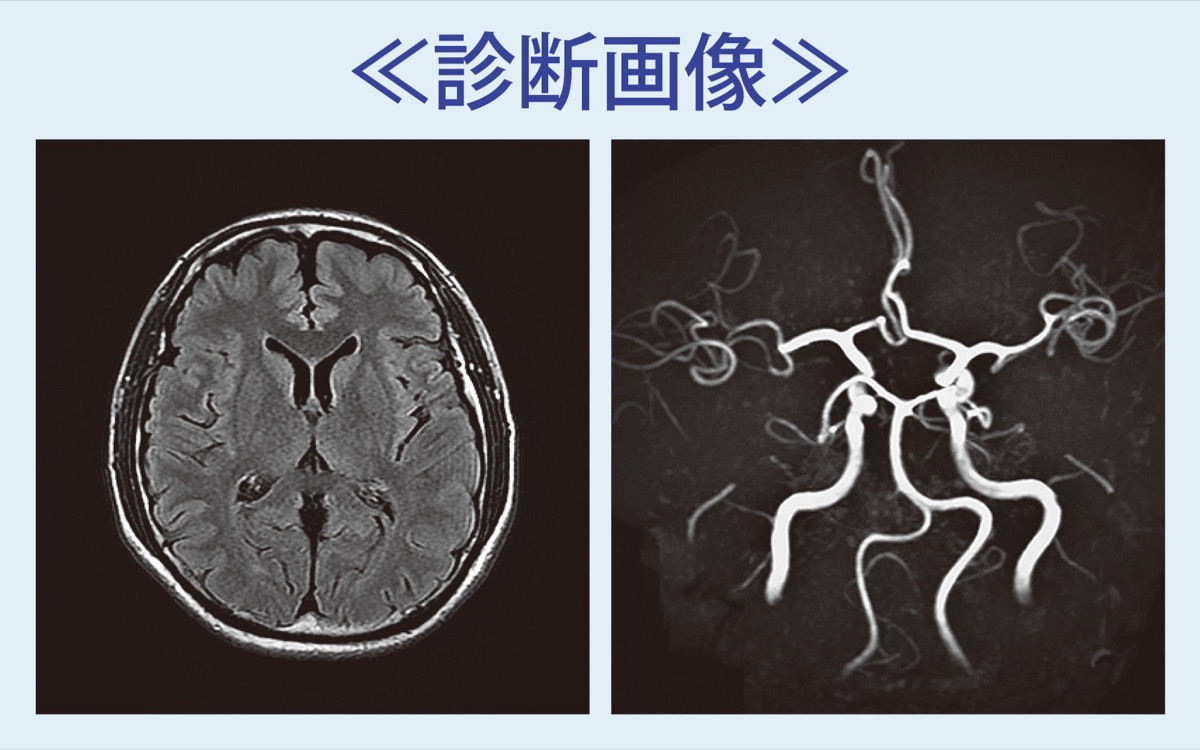

「MRI脳ドック」のすすめ

国内で年間約30万人もの人が脳の病気を新たに発症し、約10万人が命を落としているというデータがある。これを予防する手段のひとつが「脳ドック」の受診。発見できる病気にクモ膜下出血の原因となる脳動脈瘤、脳梗塞の原因となる脳血管狭窄症や虚血性変化、認知症と関連のある脳萎縮や脳腫瘍などがある。

クモ膜下出血は脳動脈瘤が破裂し、突然の激しい頭痛や意識消失で発症して3割の人が死亡する。後遺症が残ることもまれでない。高齢者だけではなく、若い人でも発症リスクがあるが、動脈瘤を見つけて適切な治療を受けることで破裂を予防できる。アルツハイマー型認知症の進行状況も把握することが可能だという。

放射線などを使わずに20分程度で検査できる「MRI脳ドック」は、これらの病気の早期発見・治療につなげるための”転ばぬ先の杖”。特に高血圧や高脂血症などの生活習慣病を抱える人や血縁者にクモ膜下出血を発症経験のある人、認知症が気になる人の受診を呼び掛けている。